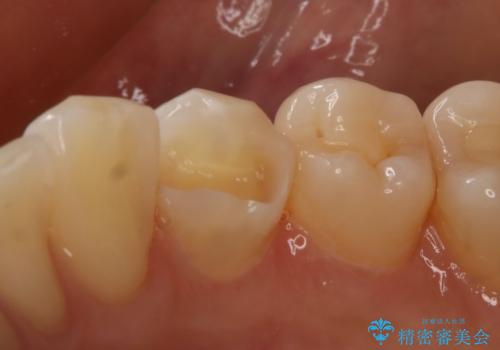

- 右下4番の虫歯治療を希望され来院された患者様です。

セラミックでの治療を希望されたため、切削量・形態を考慮しセラミックインレーでの治療を計画しました。

う蝕を除去した後、CRで裏層した上で形成、印象をしています。

装着時にはラバーダムを使用しています。